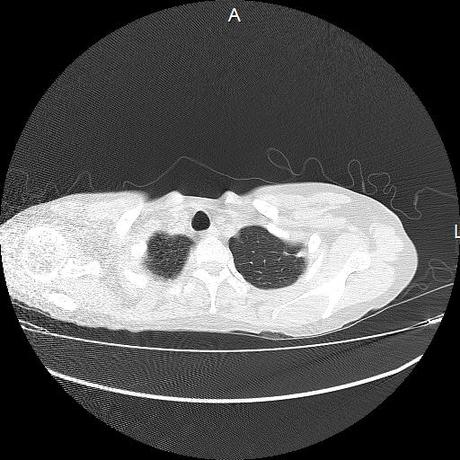

Se realiza volumen de tórax en fase simple, desde los opérculos torácicos hasta los hemidiafragmas, observándose:

El parénquima pulmonar con areas parcheadas difusas en vidrio despulido combinadas con otras areas hipodensas de baja atenuación debidas a atrapamiento aéreo y engrosamiento intersticial y zonas de fibrosis de predominio en lóbulos medios e inferiores de ambos pulmones.

La pleura se encuentra conservada, sin engrosamientos.

- LOS HALLAZGOS PUEDEN ESTAR EN RELACIÓN A NEUMOPATIA INTERSTICIAL PROBABLE ETIOLOGIA HIPERSENSITIVA VS AUTOINMUNE/BACTERIANA/FUNGICA.